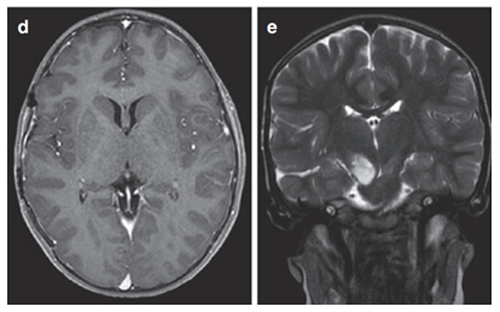

9岁男童出现左面部、上肢和下肢急性症状3周,持续轻微口齿不清超过三个月。体查发现多处咖啡色斑点和腋窝雀斑,曾诊断为注意缺陷多动障碍。

轴位MRI造影剂及冠状面T2-WI显示右侧丘脑结节状肿瘤呈环形增强。肿瘤累及内侧颞叶结构,Rutka教授制定综合治疗方案:先行经颞中回经脑室入路次全切除肿瘤,病理确诊为WHO I级毛细胞星形细胞瘤,BRAF重复融合状态阴性。免疫组化检测BRAF V600E、H3K27M均为阴性。基因检测证实NF1基因变异。

术后六个月影像显示丘脑部分切除和中脑肿瘤残留,据此制定个性化辅助治疗计划,患儿对放疗反应良好。